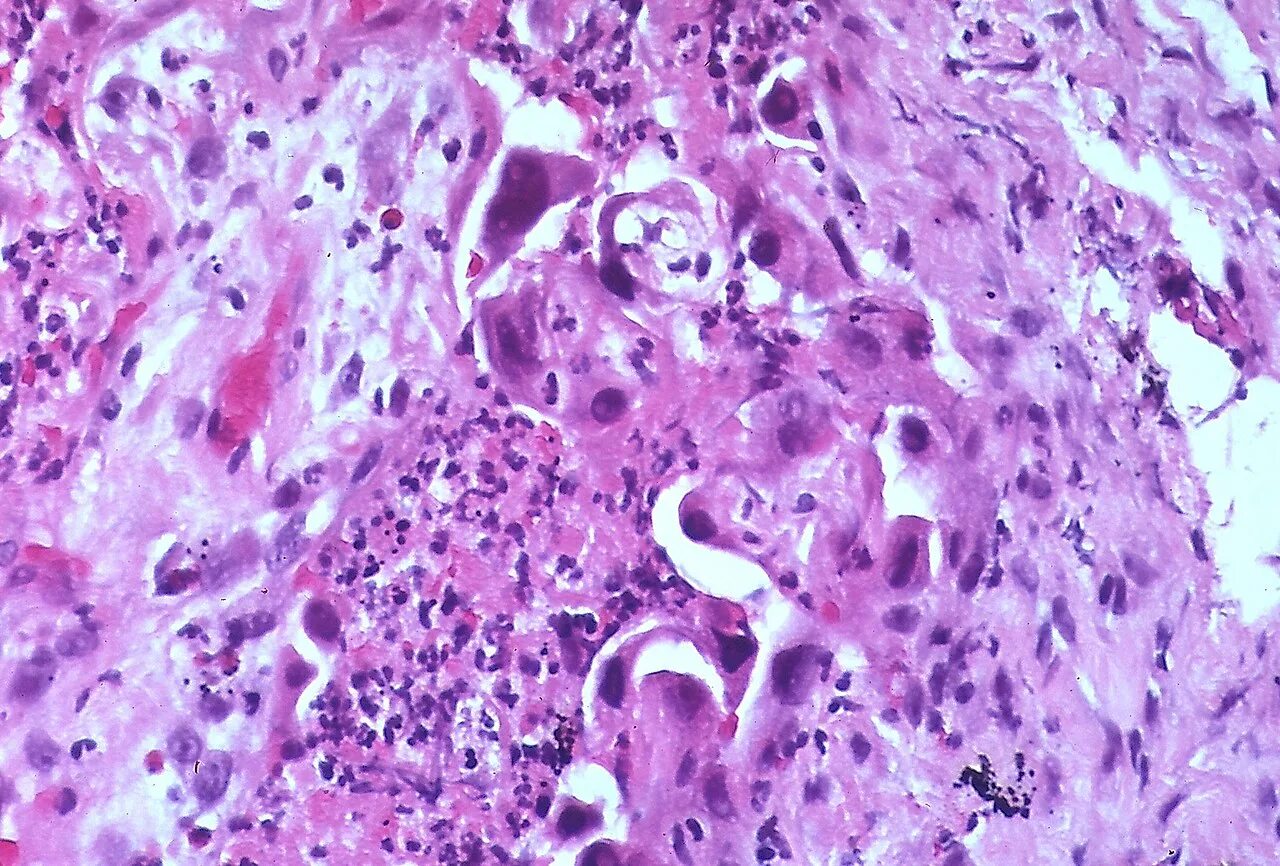

Выраженная атипия